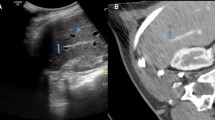

In our study, the overall technical success rate of the CT/MRI-US automatic fusion system based on vascular segmentation was 82.7% (115/139). Target tumor localization confidence and technical feasibility significantly increased after successful automatic fusion (p < 0.001). Overall technical efficacy (96.3% [78/81]) of automatic fusion-guided RFA in patients with poorly localized tumors on B mode US was similarly excellent to that in patients with well-localized tumors (97.7% [42/43]) (Appendix 4). The therapeutic outcome of the RFA procedure assisted by the automatic fusion system in our study was similar or even better in several aspects than these reported in the literature, despite the fact that there were many tumors (67.8% [103/152]) with poor conspicuity of HCCs on B mode US which may be excluded from the procedure in practice [1, 5] (Fig. 5). The mean scan duration of automatic fusion (154.4 s) was comparable to those reported by previous studies using manual fusion by experts, and it is practically acceptable when considering the duration required for patient sedation and equipment preparation [15]. Although few previous studies have reported the technical feasibility of the real-time automatic image fusion technique, our study further suggests the long-term outcomes of automatic CT/MRI-US fusion-assisted RFA in a large number of participants. Based on our study results, an automatic CT/MRI-US fusion system may contribute to the clinical adoption of fusion systems for US-guided procedures, including RFA.

A representative case of successful automatic fusion followed by complete ablation of the tumor. A A 50-year-old man presented with a 0.7 cm-sized recurred HCC at segment 8 liver dome. The initial target tumor localization confidence of the tumor was scored as ‘invisible’ (score 1) B Vascular matching was done, and automatic fusion process was successful. C Target tumor localization confidence score increased to ‘subtle localization’ (score 2) and technical feasibility increased from ‘high’ (score 3) to ‘highest’ (score 4) after the fusion process. Automatic CT/MR-US fusion-assisted RFA was done. D Successful ablation was confirmed at immediate post-procedural CT scan